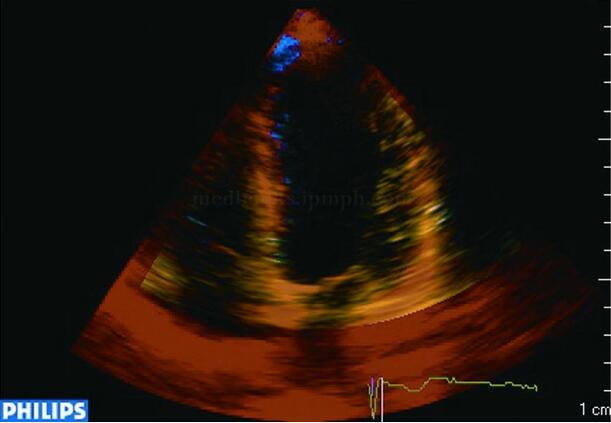

心肌声学造影是目前唯一能直接用于评价心肌微循环灌注的超声新技术,通过静脉注射含有微气泡的超声造影剂后,应用专门的超声显像技术直接观察左室心肌的微循环灌注情况。灌注正常的心肌包含足量的造影剂微气泡,二维超声图像上显示心肌回声呈较均匀一致的增强,而病变心肌由于供血量减低,局部的微气泡量减少,二维超声图像上显示局部心肌回声较正常心肌减低或回声不均匀,呈充盈缺损状态(图2‐1‐157)。如果用闪烁显像击破所有微气泡后,观察心肌微气泡的再充盈情况有助于判断潜在或轻度的心肌缺血。应用心肌声学造影无创性定量评价局部心肌血流量,可弥补冠状动脉造影不能显示心肌微循环的不足,能更准确地评价局部心肌缺血和心肌存活,具有很好的临床应用前景。

图2‐1‐157 能量心肌声学造影图像

A﹒前间壁心肌梗死患者心尖四腔心切面,左室前间壁中下段心肌造影剂充盈缺损,显示为黑色(箭头所示),表明该处心肌微循环灌注障碍;B﹒正常人心尖四腔心切面,左室前间壁中下段心肌有造影剂充盈,显示为红色(箭头所示),表明微循环灌注正常